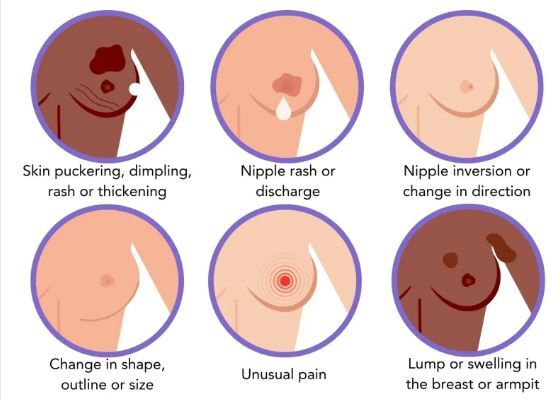

علائم مهم سرطان سینه که نادیده گرفته میشوند

به گزارش مجله خبری نگار،سرطان سینه یکی از شایعترین سرطانها در میان زنان است و تشخیص زودهنگام آن نقش حیاتی در موفقیت درمان و افزایش شانس بهبودی دارد. برخلاف تصور عمومی که تنها وجود توده را نشانه اصلی میدانند، سرطان سینه میتواند خود را با طیف وسیعی از علائم ظریف نشان دهد. آگاهی از این نشانههای هشداردهنده و حساس بودن به تغییرات بدن، به زنان کمک میکند که هرگونه مورد غیرعادی را به سرعت شناسایی کرده و برای بررسیهای بیشتر به پزشک مراجعه کنند.

علائم مهم سرطان سینه که نباید نادیده گرفته شوند

کارشناسان تأکید میکنند که اگرچه وجود توده یکی از بارزترین نشانههاست، اما سرطان سینه تنها با یک علامت بروز پیدا نمیکند. در ادامه، به چند نشانه هشداردهنده اشاره میشود که آگاهی از آنها میتواند نجاتبخش باشد:

۱. توده یا تورم در سینه یا زیر بغل

توده اصلیترین نشانه سرطان سینه است، اما ممکن است که در قسمت بالایی قفسه سینه یا زیر بغل نیز ظاهر شود. بیشتر تودهها خوشخیم هستند، اما هرگونه برجستگی جدید باید توسط پزشک بررسی شود.

۲. تغییرات در ظاهر پوست سینه

تغییر در بافت پوست، مانند چینخوردگی، فرورفتگی یا زبری شبیه پوست پرتقال، میتواند نشانه رشد سلولهای غیرطبیعی در زیر پوست باشد و نیاز به بررسی فوری دارد.

۳. تغییر در اندازه یا شکل سینهها

سینهها بهطور طبیعی دقیقاً شبیه به یکدیگر نیستند، اما تغییر ناگهانی در اندازه، برجستگی یا فرم کلی میتواند هشداردهنده باشد. متخصصان توصیه میکنند که زنان با لمس منظم سینههای خود به ظاهر طبیعی بدنشان آشنا شوند تا تغییرات غیرعادی را سریعتر تشخیص دهند.

۴. تغییر رنگ پوست

قرمزی، التهاب یا تیرگی پوست سینه از نشانههایی است که باید جدی گرفته شود؛ زیرا ممکن است که نشانه التهاب ناشی از سرطان سینه التهابی باشد.

۵. تغییر در نوک سینه

اگر نوک سینه ناگهان به داخل کشیده شود یا تغییر شکل یا موقعیت پیدا کند، این تغییر میتواند علامتی هشدار باشد. افرادی که بهصورت طبیعی نوک سینه فرورفته دارند، باید تنها به تغییرات جدید توجه کنند.

۶. جوش یا پوستهپوسته شدن اطراف نوک سینه

اگر جوشهای اطراف نوک سینه بهبود نمییابند یا پوست پوستهپوسته میشود، باید توسط پزشک معاینه شود. این علائم گاهی میتوانند نشانه سرطان پاجت سینه باشند که از ناحیه نوک سینه آغاز میشود.

۷. ترشح غیرعادی مایع از نوک سینه

در شرایطی غیر از شیردهی، خروج خودبهخودی مایع از نوک سینهها میتواند نشانهای از وجود توده در مجاری شیری باشد و نیاز به بررسی تخصصی دارد.

۸. درد مداوم در سینه یا زیر بغل

درد سینه همیشه نشانه سرطان نیست، اما درد دائمی و موضعی که با چرخه قاعدگی ارتباط ندارد یا مدام تکرار میشود، باید جدی گرفته شود.